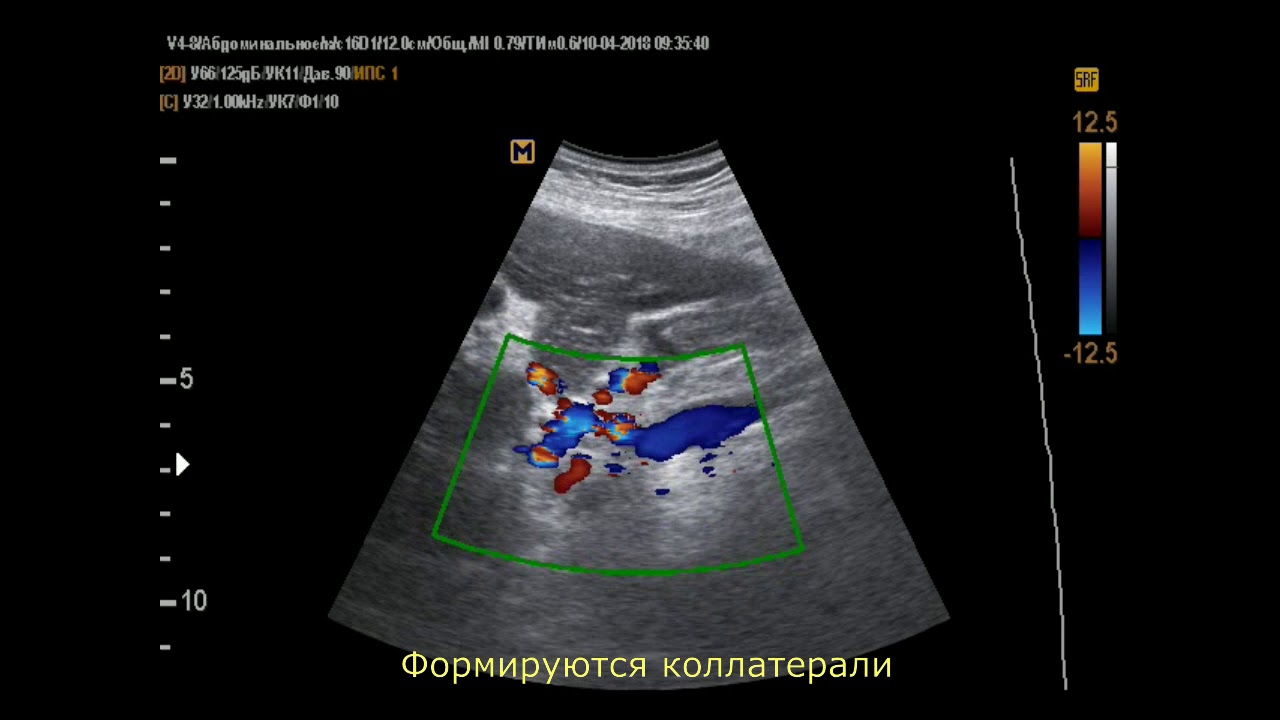

Осложнения цирроза печени